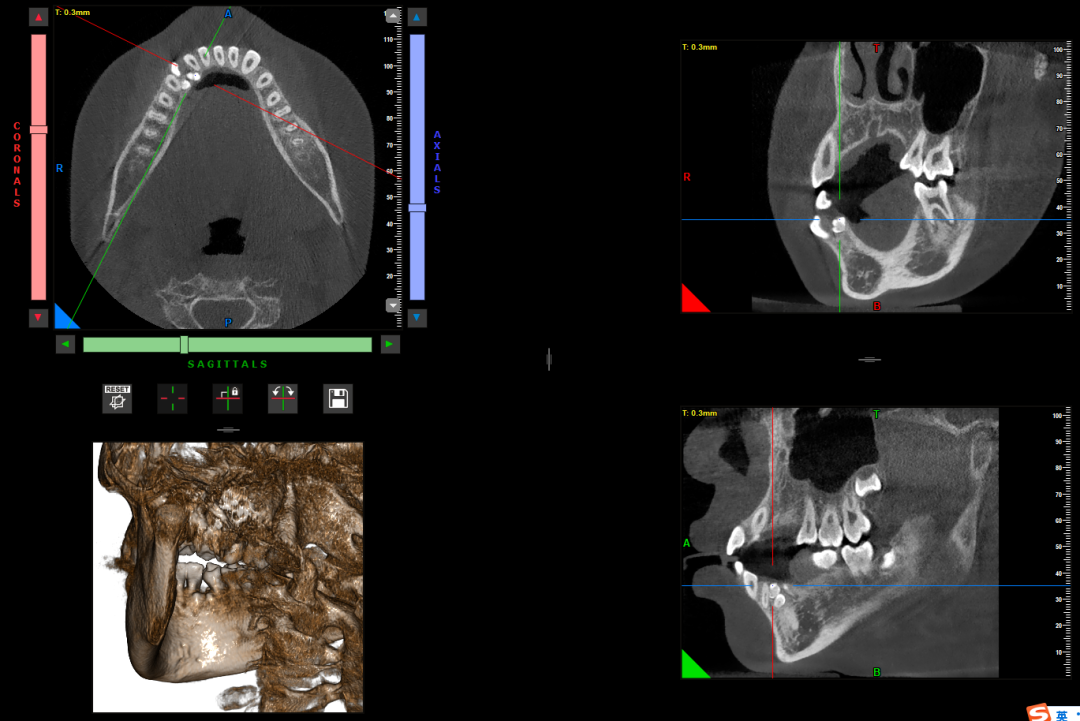

锥形束CT(CBCT)

锥形束CT是指放射线束呈锥形发出,围绕患者头部旋转获得扫描视野内的原始图像,从而进行三维观察及三维重建的数字容积体层摄影。

它可以从三维角度观察到每一颗牙齿、上下颌骨、血管神经、颞下颌关节的情况;可以清晰的观察到牙根折裂情况,囊肿的大小、位置及与牙齿牙根、神经的关系;可以显示多生牙、埋伏牙的位置关系;也能为口腔种植技术提供精准的颌骨测量指标。

CBCT可以了解多生牙的位置关系